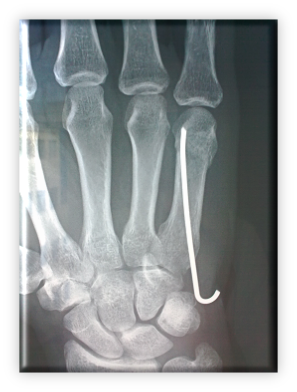

Tυπικό κάταγμα 5ου μετακαρπίου (μετακαρπίου που αντιστοιχεί στο μικρό δάκτυλο), υποκεφαλικό, με παλαμιαία παρεκτόπιση αφού το περιφερικό κομμάτι παρεκτοπίζεται προς τα κάτω. Ο μηχανισμός κάκωσης είναι αυτός της πρόσκρουσης της κεφαλής του 5ου μετακαρπίου με την άκρα χείρα σε γροθιά ( συνήθως crosse). Συμβαίνει συχνά σε αθλητές πολεμικών τεχνών, κυρίως όταν σε αυτές δεν χρησιμοποιούνται γάντια. Το σημαντικότερο στην κλινική εξέταση είναι η διαπίστωση αν υπάρχει στροφική παραμόρφωση του μικρού δακτύλου, οπότε οπωσδήποτε χρειάζεται χειρουργείο, ή όχι.

Η αντιμετώπιση συνίσταται αρχικά σε κλειστή ανάταξη με μηχανισμό αξονικής ραχιαίας δύναμης στη πρώτη φάλαγγα με τη μετακαρπιοφαλαγγική σε κάμψη 90 μοιρών. Ακολουθεί ακινητοποίηση σε νάρθηκα με το δάκτυλο σε έκταση και τη μετακαρπιοφαλαγγική 90 μοίρες κάμψη, για 3 εβδομάδες. Σημειώνεται ότι πρόκειται για πολύ ασταθές κάταγμα που παρά την αρχική ανάταξη και ακινητοποίηση στο νάρθηκα , η παρεκτόπιση είναι συχνή. Στην περίπτωση αυτή και για ασθενείς χωρίς ιδιαίτερες απαιτήσεις, μια γωνίωση μέχρι 30 μοίρες μπορεί να γίνει αποδεκτή χωρίς ιδιαίτερα λειτουργικά προβλήματα. Παραμένει όμως άλλοτε σε άλλο βαθμό μια μόνιμη διόγκωση στην περιοχή που μπορεί να δημιουργήσει αισθητικό πρόβλημα.

Για ασθενείς λοιπόν που η αισθητική της άκρας χείρας είναι σημαντική, για ασθενείς που ο χρόνος είναι πολύ σημαντικός (3 εβδ. ακινητοποίηση), για ασθενείς με στροφική παραμόρφωση, για ανοικτά κατάγματα όπου υπάρχει επικοινωνία του οστού με τον αέρα και για ασθενείς που έχουν ιδιαίτερες απαιτήσεις από τα χέρια τους, όπως μουσικοί, πιανίστες, χειρουργοί, αθλητές υψηλού επιπέδου, πυγμάχοι κτλ, συνιστάται χειρουργική θεραπεία και άμεση κινητοποίηση. Η άμεση κινητοποίηση μετά το χειρουργείο μειώνει τις πιθανότητες δυσκαμψίας της άρθρωσης.

Οι εναλλακτικές μέθοδοι χειρουργικής θεραπείας είναι ανοικτή ανάταξη και εσωτερική οστεοσύνθεση με πλάκα και βίδες, κλειστή ανάταξη και ενδομυελική οστεοσύνθεση με σύρμα, εξωτερική οστεοσύνθεση, έμμεση οστεοσύνθεση με βελόνες διά του 4ου μετακαρπίου. Η επιλογή εξαρτάται από την «προσωπικότητα» του κατάγματος.